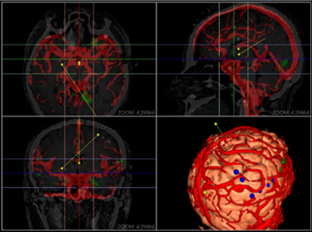

同方鼎欣專業影像產品群是直接面向神經外科、骨科、血管分析等臨床科室的輔助診療、手術計劃、分析的解決方案,系統整合了醫療影像的導入、二維閱片、三維重建、序列配準融合、自動分割、自動計算、手術計劃等一系列功能。充分滿足了臨床科室的專業需求,提供了完整、強大、可靠、方便的工具平臺。

融合(Fusion)、融合結果三維重建;

3D序列血管分段及管理;

血管中心線勾畫,曲面重建(CPR);

心腦血管分析模塊